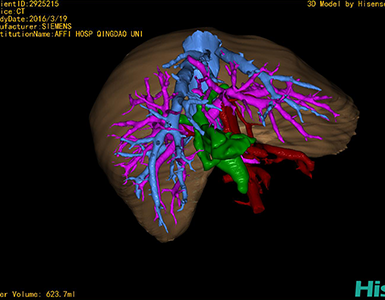

CT结果输入海信CAS系统后行3D重建及手术规划后,于2016-3-22全麻下行“胆总管囊肿切除+胆囊切除+胆总管-空肠吻合术”手术治疗:

术前三维重建及手术方案设计:

将0.625mm双源薄层CT资料的静脉期和动脉期Dicom格式文件导入海信CAS系统。

通过调节窗宽窗位调整CT序号,对肝实质,胆囊,下腔静脉,肿瘤,肝动脉、门静脉及肝静脉等进行三维重建;系统自动计算肝脏体积。

术前手术方案的规划。

术前三维重建:

重建图片